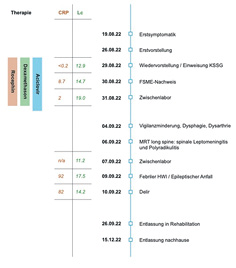

Wir berichten über einen 23-jährigen Patienten, der sich aufgrund persistierender Kopfschmerzen sowie Fieber und Erbrechen in der Hausarztpraxis vorstellte. Im weiteren Verlauf kamen eine rechtsbetonte Tetraparese, eine Dysphagie sowie eine Dysarthrie hinzu und es kam zu einem generalisierten tonisch-klonischen Krampfanfall. Weitere Abklärungen bestätigten eine FSME-Enzephalomyelitis und Polyradikulitis. Auch nach zweimonatiger Rehabilitation blieben beim ungeimpften Patienten sowohl neuropsychologische wie auch fokal-neurologische Residuen bestehen.

Aufgrund des sichtlich reduzierten Allgemeinzustandes des Patienten mit Kopfschmerzen sowie Erbrechen ohne eindeutigen Fokus und Bestehen eines möglichen Meningismus’ erfolgte die notfallmässige Zuweisung auf die Notfallstation eines Zentrumsspitals zur weiteren Diagnostik und Therapie. Durch die Angehörigen wurde dort ergänzend eine vermehrte Vergesslichkeit des Patienten in letzter Zeit beschrieben. Wie sich herausstellte, war der Patient nicht gegen FSME geimpft. In der neuerlichen neurologischen Beurteilung fielen sodann zusätzlich ein Absinken des rechten Armes (ohne Pronation) im Vorhalteversuch sowie symmetrisch schwache Muskeleigenreflexe auf.

Sowohl eine Computertomografie (CT) des Neurocraniums als auch die ergänzende CT-Angiographie waren ohne pathologische Befunde. Nach wiederholt frustraner Lumbalpunktion erfolgte bei dringendem Verdacht auf eine infektiöse ZNS-Erkrankung eine empirische Therapie mit Ceftriaxon, Dexamethason sowie Aciclovir. MR-tomografisch zeigte sich sodann ein diskret vermehrtes Enhancement zerebellär beidseits, passend zu einer Leptomeningitis (Abbildung 2).

In der im Verlauf erfolgreich durchgeführten Liquoranalyse (Tabelle 2) war eine Pleozytose mit erhöhtem Proteinanteil sichtbar, bei einer leicht- bis mittelschweren Störung der Bluthirnschranke. Zweizeitig bestimmte FSME-Serologien (sowohl IgM- als auch IgG-Antikörper) fielen jeweils positiv aus (mit deutlichem Titeranstieg (Ausgangswert IgG-Antikörper: 159 U/ml; im Verlauf 1756 U/ml)), während der HSV-Typ 1/2- sowie VZV-PCR negativ ausfiel (Tabelle 3). Die empirische Therapie mit Rocephin, Aciclovir sowie Dexamethason wurde folglich gestoppt.

Bereits zu Beginn erfolgte eine Verlegung des Patienten auf die Intensiv- und Pflegestation wo der Patient im Verlauf eine zunehmende rechts- und proximalbetonte Tetraparese (Armabduktion rechts M2, Hüftbeuger M3, sonst M4-5) entwickelte, was bei erhaltenen bis lebhalten Reflexen im Rahmen einer Enzephalomyelitis interpretiert wurde. Der Allgemeinzustand des Patienten verschlechterte sich sodann erneut, wobei es im Verlauf passend zu einer Enzephalopathie zu einer Vigilanzminderung mit Benommenheit und zu einer Dysarthrie sowie Dysphagie kam, weshalb eine Intubation sowie später eine Tracheotomie erforderlich wurden. Erschwerend kam ein Harnwegsinfekt dazu, welcher den erneuten Einsatz von Antibiotika (Piperacillin/Tazobactam) während einer Woche erforderlich machte. Nach Auftreten eines generalisierten tonisch-klonischen Anfalls zeigte eine durchgeführte Bildgebung mittels CT des Neurocraniums keine neuen Aspekte. Ein ergänzende Magnetresonanztomografie (MRT) long spine zeigte den Befund einer spinalen Leptomeningitis sowie einer Polyradiukulitis (Abbildung 3 und 4). Ebenfalls bestand eine motorische Unruhe im Sinne einer Akathisie. Es erfolgte eine weiterführende symptomatische sowie supportive Therapie, worunter es zu einer Besserung der Beschwerden kam. Nach 4 Wochen, während denen der Patient 18 Tage IPS-pflichtig war, konnte dieser in stabilem Allgemeinzustand in die Rehabilitation entlassen werden. Während den 8 Wochen der stationären Rehabilitation wurde die initial noch bestehende Dysphagie mittels Logopädie deutlich verbessert. Obwohl ein selbständiges Gehen ohne Hilfsmittel nach Absolvierung der Rehabilitation wieder möglich war, persistierten eine verminderte Schritthöhe sowie fehlende Schutzschritte. Motorisch bestand zudem weiter eine starke Einschränkung der Abduktion des rechten Armes – ein Aufstehen vom Boden ohne Hilfsmittel war zudem weiterhin nicht möglich.